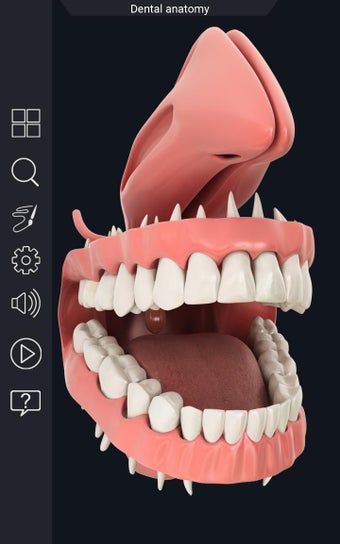

Esta aplicación es un modelo 3D de los dientes, que contiene muchas partes y muestra las condiciones dentales. Cada parte tiene un nombre y una función. Puedes mover la cámara alrededor del modelo para obtener una vista de 360° de las diferentes partes. Puedes hacer zoom para ver mejor cada parte. También puedes rotar la cámara para obtener una vista diferente del modelo.